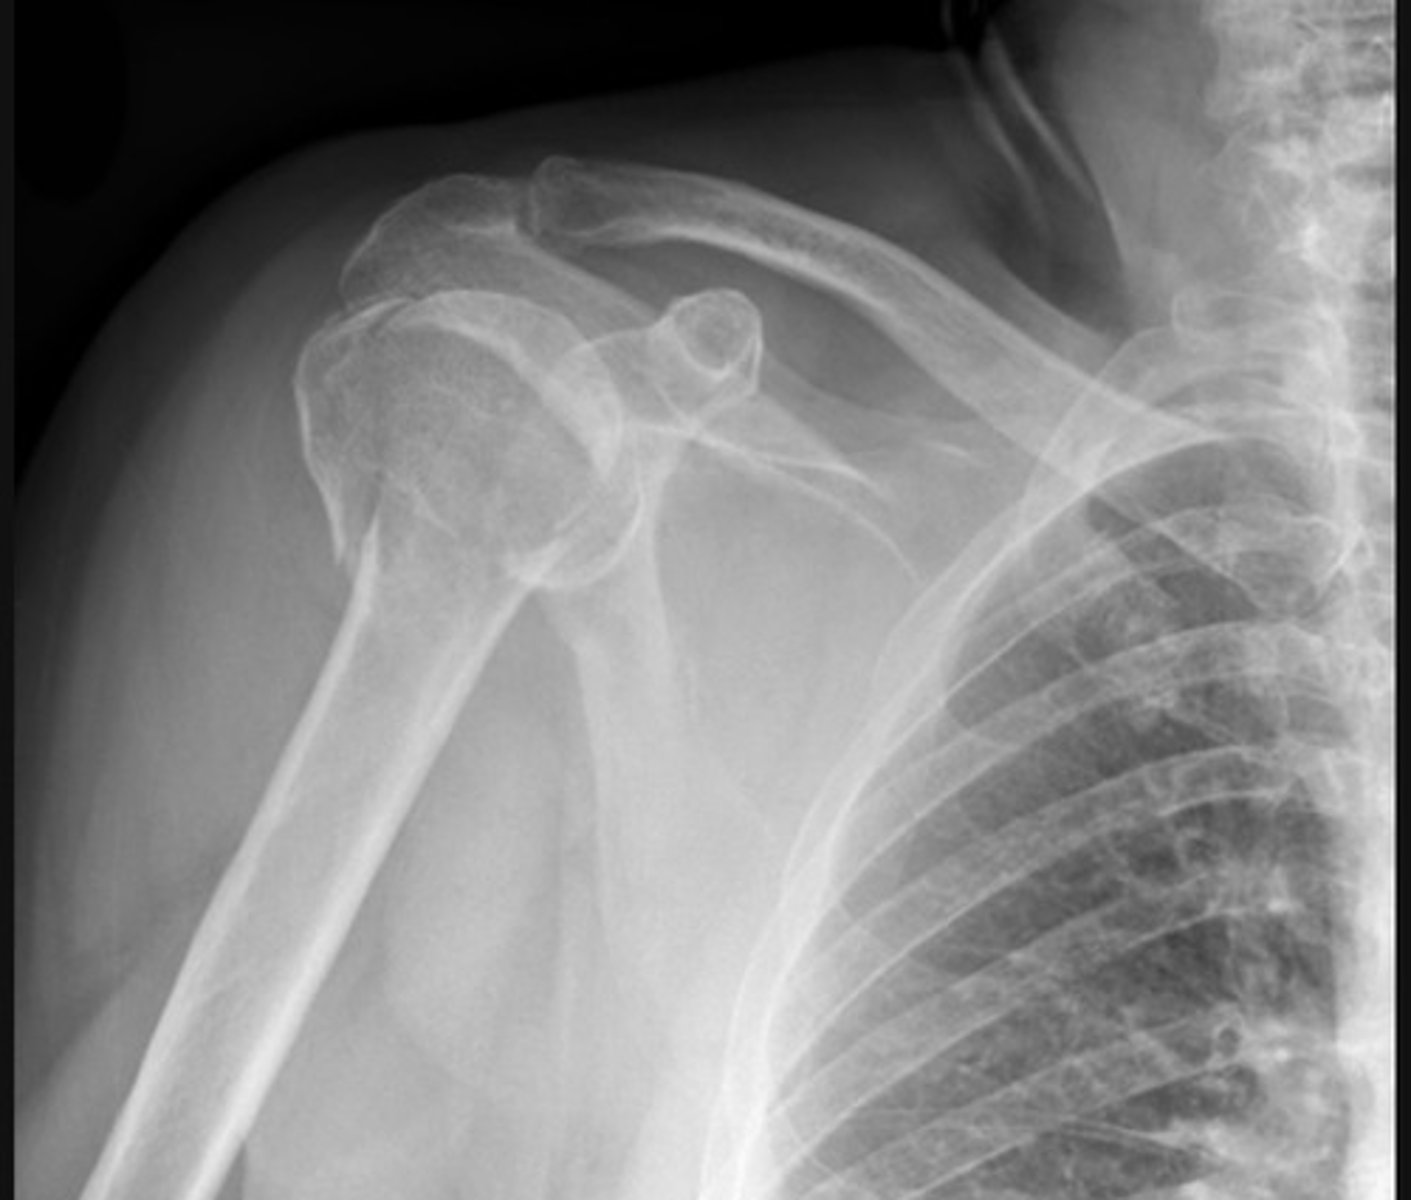

Posterior dislocation, 'lightbulb sign'